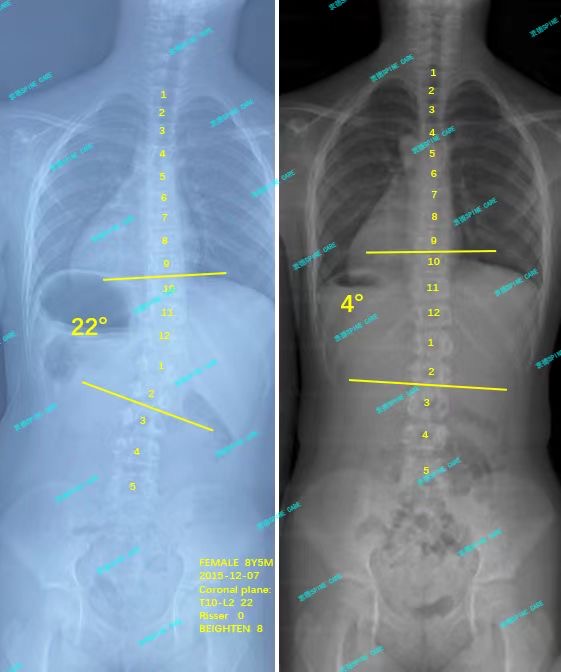

衷德脊柱,我们只关注侧弯保守治疗~

Zhongde Spine, bending no breaking ~